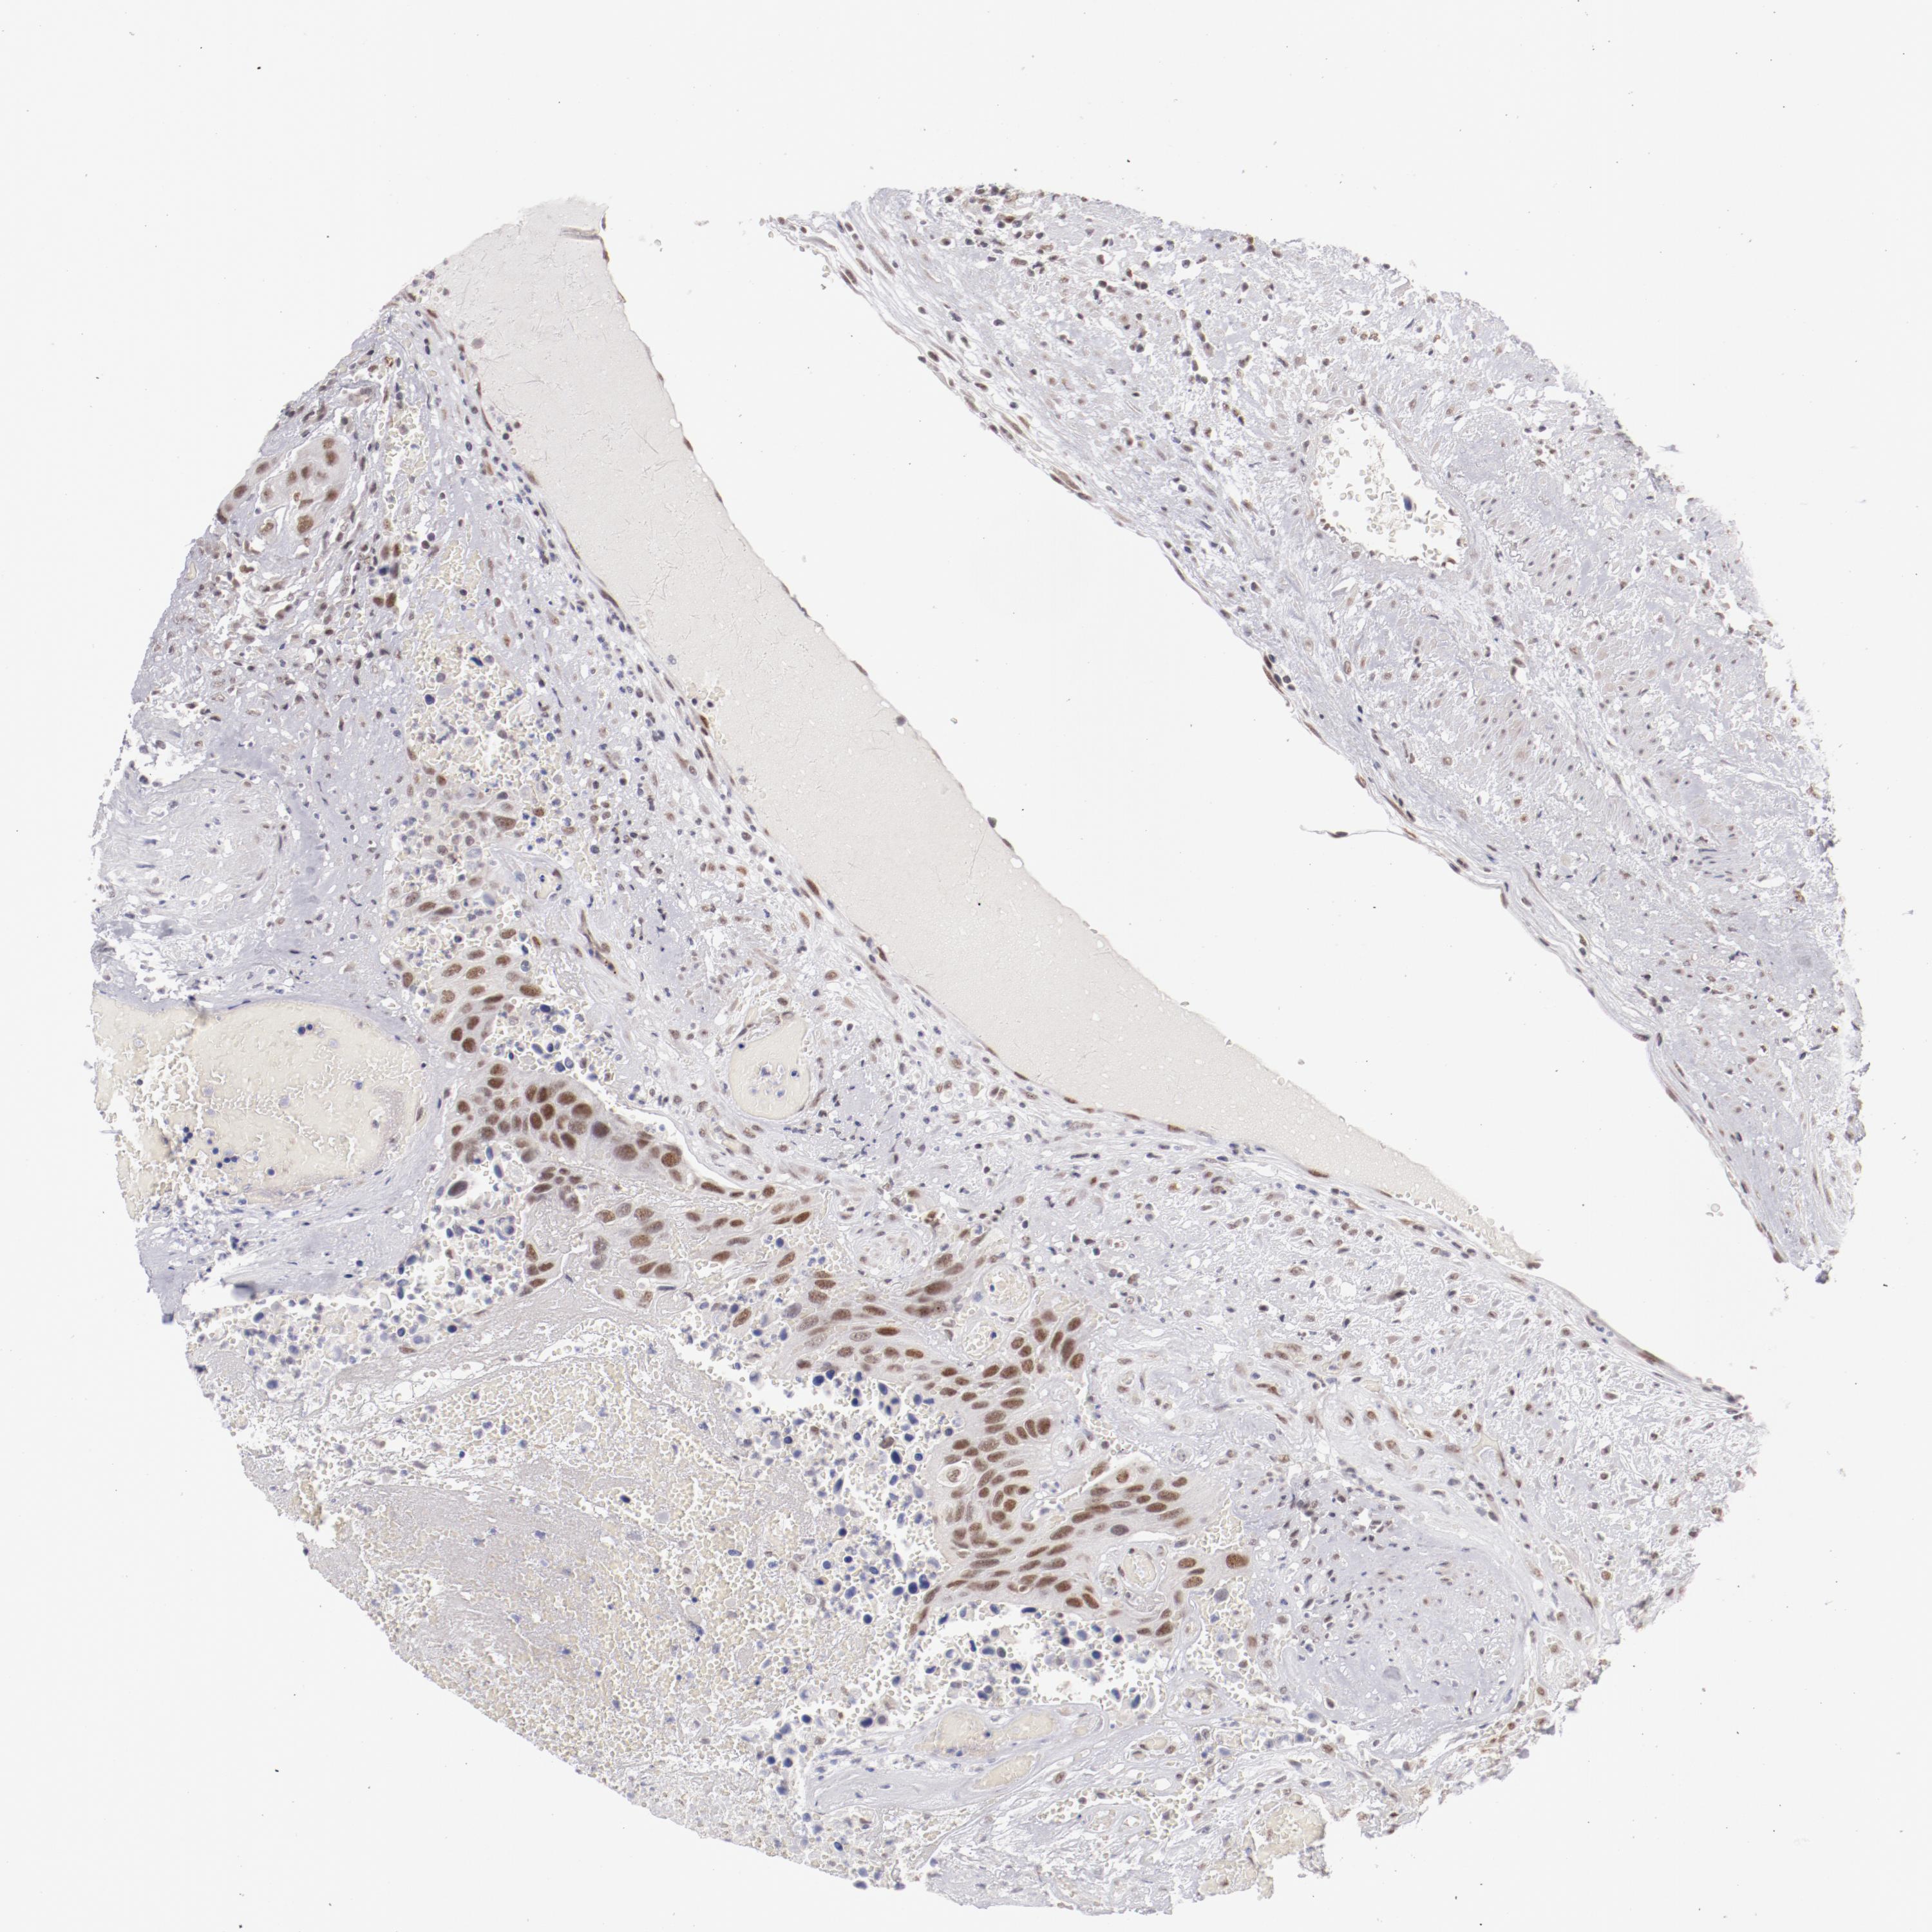

UROTHELIAL CANCER - Protein expressioni

A mouse-over function shows sample information and annotation data. Click on an image to view it in a full screen mode. Samples can be filtered based on level of antibody staining by selecting one or several of the following categories: high, medium, low and not detected. The assay and annotation is described here.

Note that samples used for immunohistochemistry by the Human Protein Atlas do not correspond to samples in the TCGA dataset.

Antibody stainingi

Antibody staining in the annotated cell types in the current human tissue is reported as not detected, low, medium, or high, based on conventional immunohistochemistry profiling in selected tissues. This score is based on the combination of the staining intensity and fraction of stained cells.

Each image is clickable and will lead to virtual microscopy that enables deeper exploration of all samples and also displays staining intensity scores, fraction scores and subcellular localization as well as patient and tissue information for each sample.

Antibody HPA001912

Staining

High

Medium

Low

Not detected

Intensity

Strong

Moderate

Weak

Negative

Quantity

>75%

75%-25%

<25%

None

Location

Nuclear

Cytoplasmic/membranous

Cytoplasmic/membranous,nuclear

Urothelial carcinoma, High grade

Urothelial carcinoma, Low grade